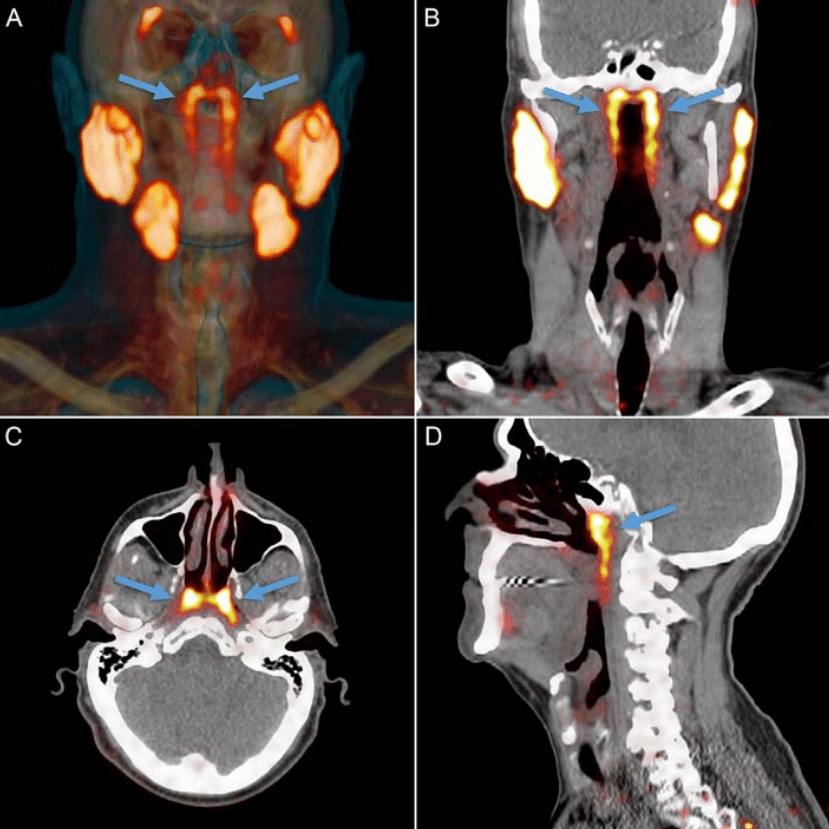

Enquanto estudavam o câncer, eles realizaram tomografias computadorizadas e tomografias por emissão de pósitrons (PET) em pacientes que haviam recebido injeções de glicose radioativa, o que teoricamente fazia com que os tumores aparecessem brilhando nas tomografias.

Ao realizar os exames, a equipe notou que duas áreas dentro das cabeças dos pacientes estavam brilhando mais do que o previsto – e, por fim, descobriram que havia um conjunto secreto de glândulas salivares escondidas ali.

A equipe decidiu dar a elas um nome apropriado: glândulas salivares tubárias, já que elas são encontradas atrás do nariz e no espaço onde a cavidade nasal se junta à garganta. Quanto à sua função, as glândulas ‘lubrificam e umedecem a área da garganta atrás do nariz e da boca’.